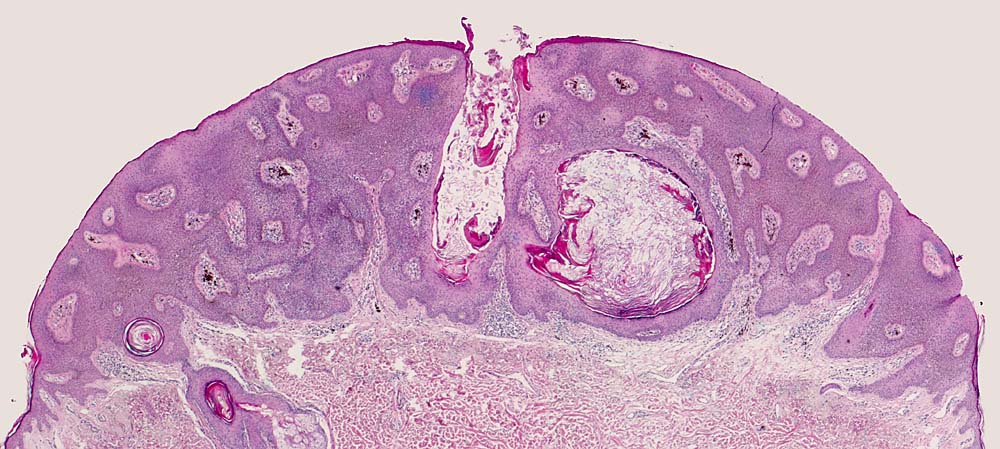

Basel 2BA/ Seborrhoische Keratose

Seborrhoische Keratose

Histologie:

Die grosse makroskopische Vielgestaltigkeit widerspiegelt sich auch in einer variablen Histologie. Unterschieden werden mehrere histologische Subtypen der seborrhoischen Keratose: Hyperkeratotischer Typ (> 3435), akanthotischer Typ (Kurspräparat), klonaler Typ (> 7284) (> 7285), irritierte seborrhoische Keratose (> 3353) (> 3356). Typisch für seborrhoische Keratosen sind umschriebene Wirbelbildungen von Tumorzellen, sogenannte squamous eddies (> 8065). Der retikuläre Typ (> 7838) entwickelt sich in chronisch UV exponierter Haut meist im Gesicht und geht oftmals hervor aus einer solaren Lentigo (> 7839)

Morphologische Merkmale:

• Erhabener (=exophytischer) Tumor

• Verdickte Epidermis (Akanthose)

• Keratingefüllte Epidermisinvaginationen und Hornzysten mit konzentrisch geschichteten Hornlamellen.

• Vernetzte Zellstränge bestehend aus monomorphen basaloiden zytoplasmaarmen Plattenepithelzellen.

• Herdförmige starke braune Pigmentierung der Tumorzellen.

• Perivaskulär betonte, oberflächlich dermale lymphohistiozytäre Entzündung mit Melanophagen. Das sollte der Kliniker dem Pathologen mitteilen: